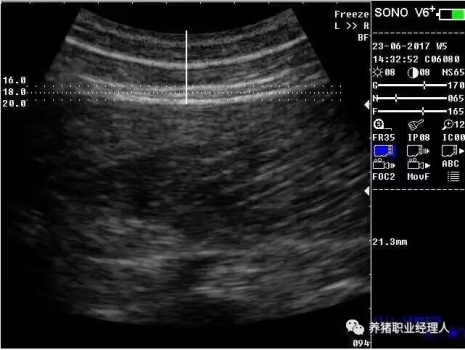

北京宏牧偉業(yè)網(wǎng)絡(luò)科技有限公司 版權(quán)所有(京ICP備11016518號(hào)-1)